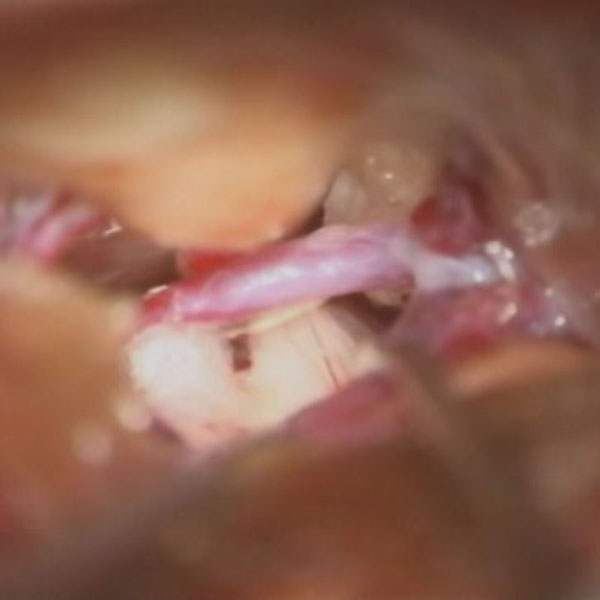

手術中

処置前

処置後